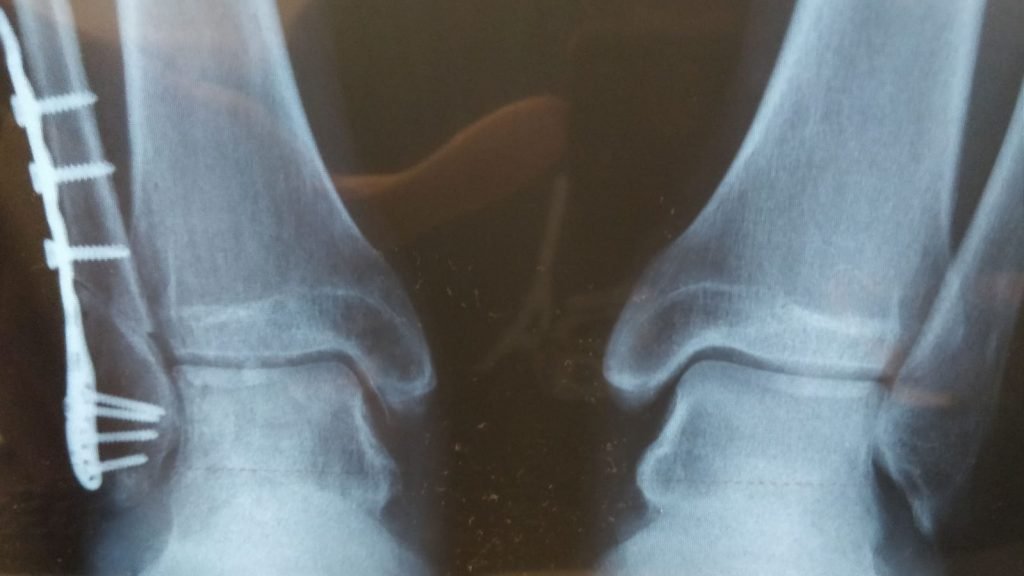

Tahun ini kami hanya bekerja sama secara fisik di kantor kami di bulan Januari. Operasi pergelangan kaki (berhasil, omong-omong) menyebabkan David mengambil cuti di awal Februari. Kemudian penguncian datang pada bulan Maret, setidaknya bagi kami di sini di Spanyol.